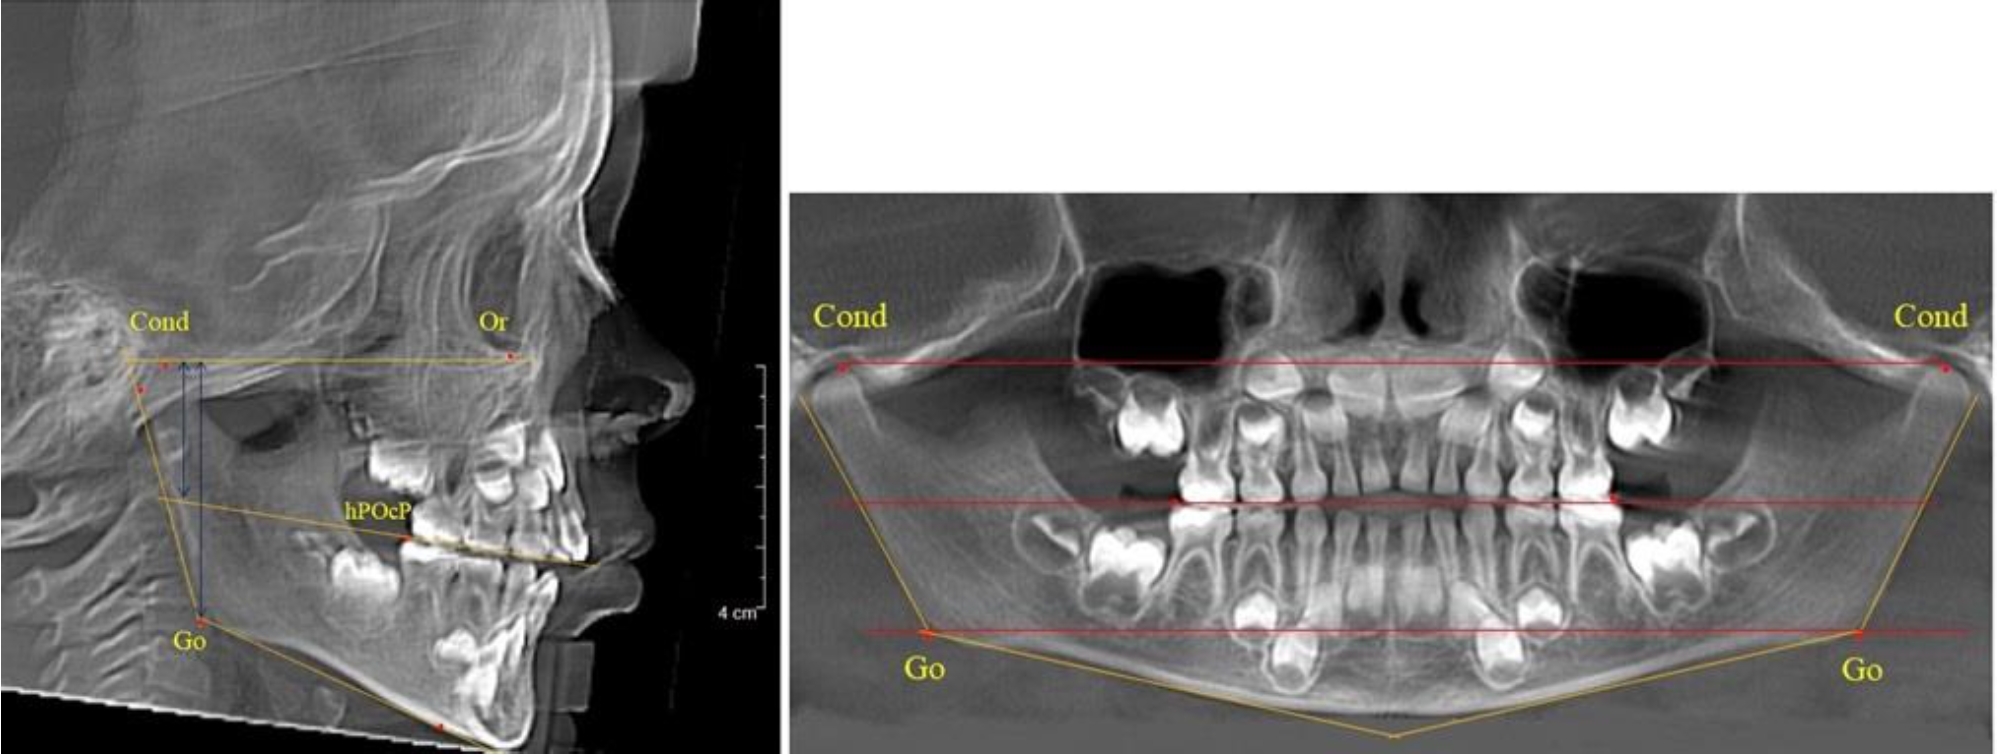

В 5-й группе были проанализированы 14 комплектов рентгенограмм, что составило (13,21 ± 3,29) % от общего числа. На всех рентгенограммах отмечен очередной этап подъема высоты прикуса, обусловленный прорезыванием вторых постоянных моляров. Окклюзионная линия делила ветвь на два отдела (рис. 5).

Рис. 5. ТРГ и ОПТГ пациента после смены молочных зубов и прорезывания вторых постоянных моляров

Высота ветви у детей 5-й группы составляла (62,87 ± 3,62) мм, что было достоверно больше, чем у детей других групп (р ˂ 0,05). При этом высота верхней окклюзионно-суставной части была (40,23 ± 2,01) мм, а нижней – (22,64 ± 1,78) мм. Высота верхней части была вдвое больше нижней, что и определяло особенности соразмерности частей ветви нижней челюсти в анализируемый возрастной период.

Относительные показатели соразмерности частей ветви нижней челюсти показали, что отношение высоты верхней части ветви к нижней в среднем составляло 1,78 ± 0,18. Отношение общей высоты ветви к верхней ее части составляло 1,56 ± 0,12, а отношение общей высоты ветви к нижней ее части было 2,78 ± 0,14, что и определяло особенности соразмерности частей ветви нижней челюсти в анализируемый возрастной период.